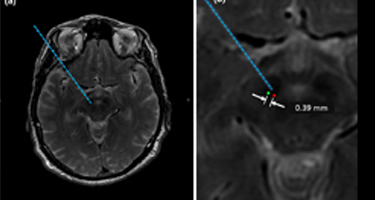

DEEP BRAIN STIMULATION (DBS) WITH OMNITOM

Watch Dr. Kim Burchiel, John Raaf Professor and Head Division of Functional Neurosurgery from Oregon Health and Science University pioneer "asleep" DBS for patients with Parkinson's and essential tremors. WATCH NOW >